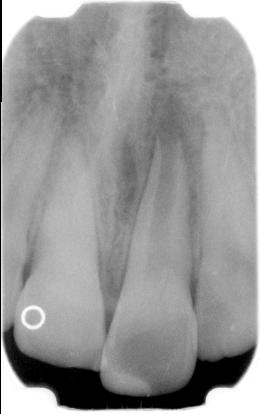

De open apex

laatste xf is een controlefoto 1 jaar na de behandeling